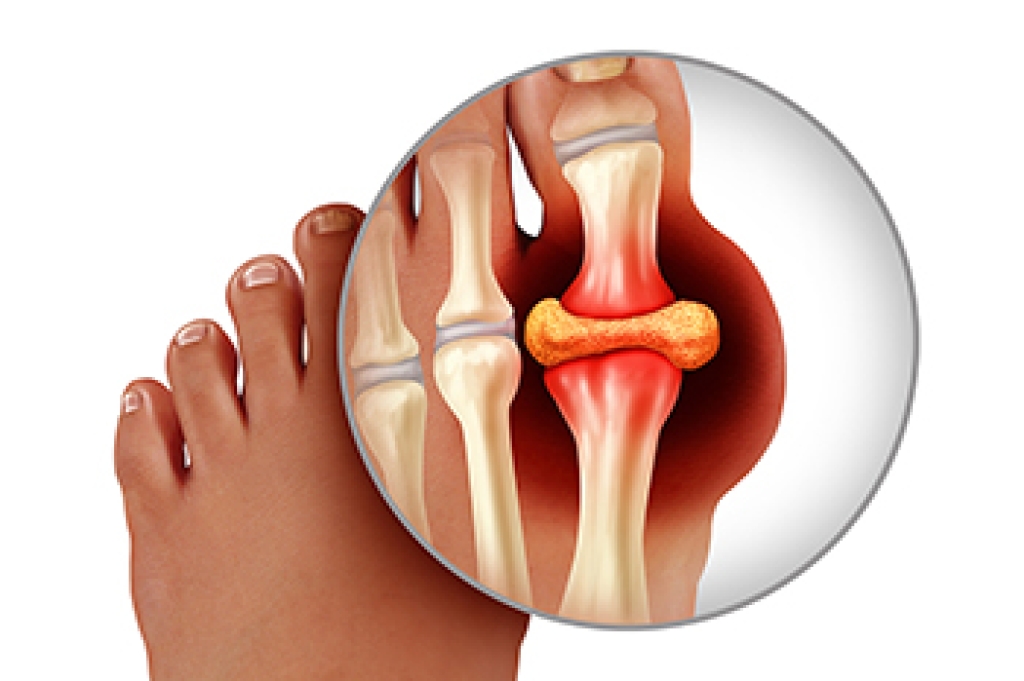

Ankle sprains are the result of a tear in the ligaments within the ankle. These injuries may happen when you make a rapid shifting movement while your foot is planted. A less common way to sprain your ankle is when your ankle rolls inward while your foot turns outward.

- Pain at the sight of the tear

- Bruising/Swelling

- Ankle area is tender to touch

- In severe cases, may hear/feel something tear

- Skin discoloration